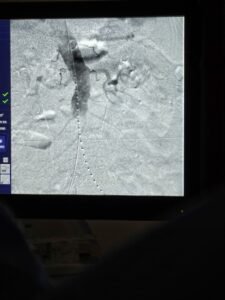

EVAR (endovaskularna rekonstrukcija aneurizme) minimalno je invazivna metoda kojom se kroz male rezove u preponama, uz rendgensko navođenje, u krvnu žilu postavlja stent-graft. Ta potporna struktura preusmjerava protok krvi i sprječava puknuće aneurizme.